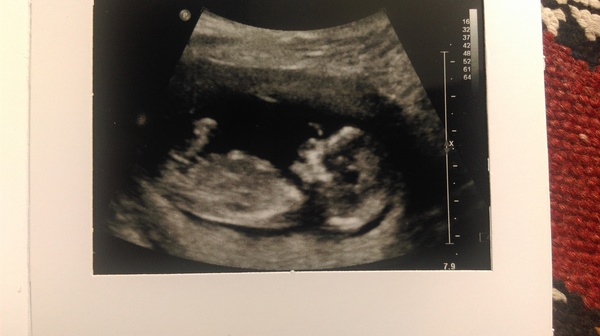

Scan went well today! Reception desk didn't pass info through to ultrasound dept that I'd arrived so scan ended up being almost an hour late. Not good when you're desperate for a wee but they apologised a lot.

Baby was wriggling away and gave us a few waves too. Measurements have moved my date a bit, thought I was due 16th, now due on 12th Jan.

Lovely scan picture maybe - congratulations on the scan.

Great news on your scan maybe Glad everything is well Grin Lovley picture!

Congrats Maybe - glad you got a few waves! You're now due the day before me Smile

maybemrs glad your scan went well, counting the hours till mine, itsiteven encouraging seeing lots of lovely scan pics!

Congrats maybe on your scan. We share a due date.